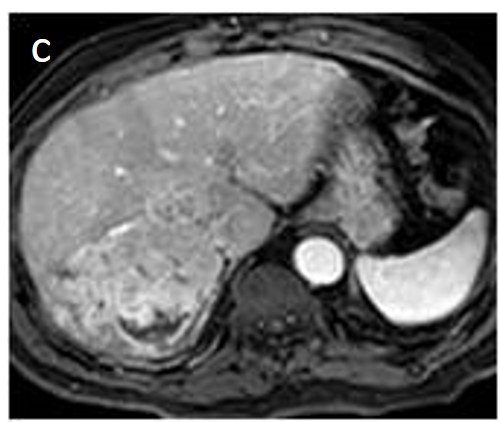

The presence of a capsule (Figure 12) is a major finding according to LI-RADS, but not EASL. The capsule is a characteristic feature of progressed HCC and is absent in dysplastic nodules or early HCCs. It shows low T1 and T2 signal intensity and enhancements on the portal and delayed phase at 3 min after contrast injection (or transitional phase if hepatospecific contrast agent is used); on the contrary, corona enhancement occurs earlier on the arterial phase. A capsule should be thicker than the fibrous septa of cirrhosis, which also show delayed enhancement. An intact capsule on imaging has been associated with lower recurrence rates after treatment [137], while extracapsular tumor extension predicts poor survival [138]. It should be stressed, however, that an encapsulated progressed HCC has a worse prognosis than an unencapsulated early HCC; the presence of a capsule confers a better prognosis only when the encapsulated tumor is compared to HCCs of a similar size and grade with breached capsules or without a capsule.

Figure 12. A large HCC is depicted in the right liver lobe of this 81-year-old man. The tumor is surrounded by a capsule, nicely seen as a thin, low signal line on the fat-suppressed T2 sequence (arrowheads) (a) and shows inhomogeneous but predominantly high T2 signal intensity. Areas of fat are clearly shown in the in/out of phase images (asterisk) (b,c). This marked heterogeneity is known as the “mosaic” pattern. After contrast administration, mottled arterial enhancement is noted (d); definite wash-out and capsular enhancement (arrows) are seen on the portal phase (e).